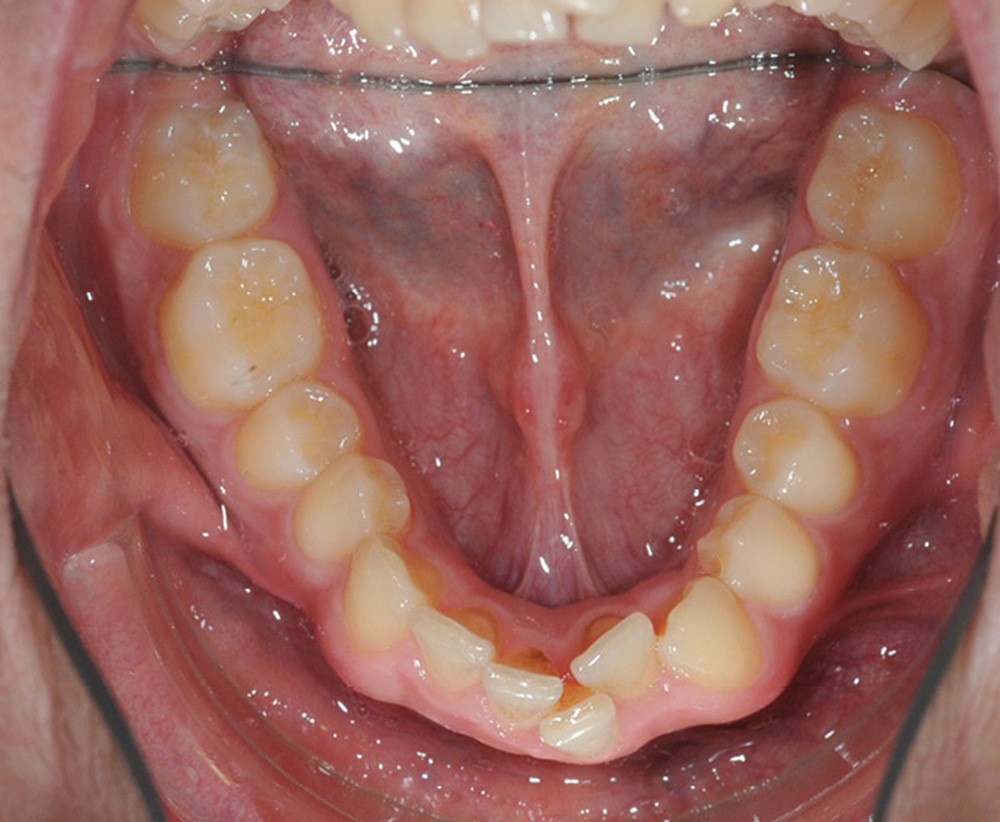

C’est à ces questions que nous permettront de répondre les deux premiers conférenciers, parodontologistes : le Dr Béatrice Straub nous présentera le renfort parodontal minéralisé, technique qu’elle a développée et pratique depuis de nombreuses années, pour éviter les préjudices des mouvements orthodontiques à risque, notamment lors des décompensations préchirurgicales (fig. 1a-d) ; le Pr Anton Sculean abordera le thème des greffes, avec leurs indications, les différentes techniques à privilégier et illustrera ses propos par de nombreux cas cliniques aux résultats esthétiques impressionnants.

Le début et milieu d’après-midi seront consacrés à l’empreinte numérique, désormais utilisée pour les empreintes d’étude, les set-up, le thermoformage. Les Drs Guillaume Lecocq et Stéphane Desplanques monteront le thermoformage et comment ces empreintes numériques peuvent permettre de confectionner des appareils vestibulaires, linguaux, voire des aligneurs (fig. 1 et 2).